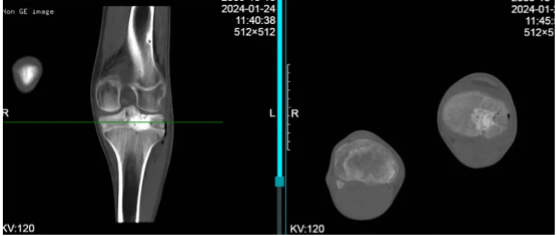

影像检查:

膝关节X线:左胫骨近端骨质密度不均影,可见溶骨性病灶改变,符合植骨后病灶复发。

CTA: 左侧胫骨平台可见团片状稍低密度骨质破坏影,直径约3cm,累及关节面,其内可见相邻腘动脉分支参与供血。

MRI:左侧胫骨上端占位,范围约30*30*20mm,T1WI等低信号,T2WI等高信号,边界较清楚,增强后轻度不均匀强化,周围骨髓及软组织肿胀。内外半月板、前后交叉韧带及内外侧副韧带形态、信号均未见异常。